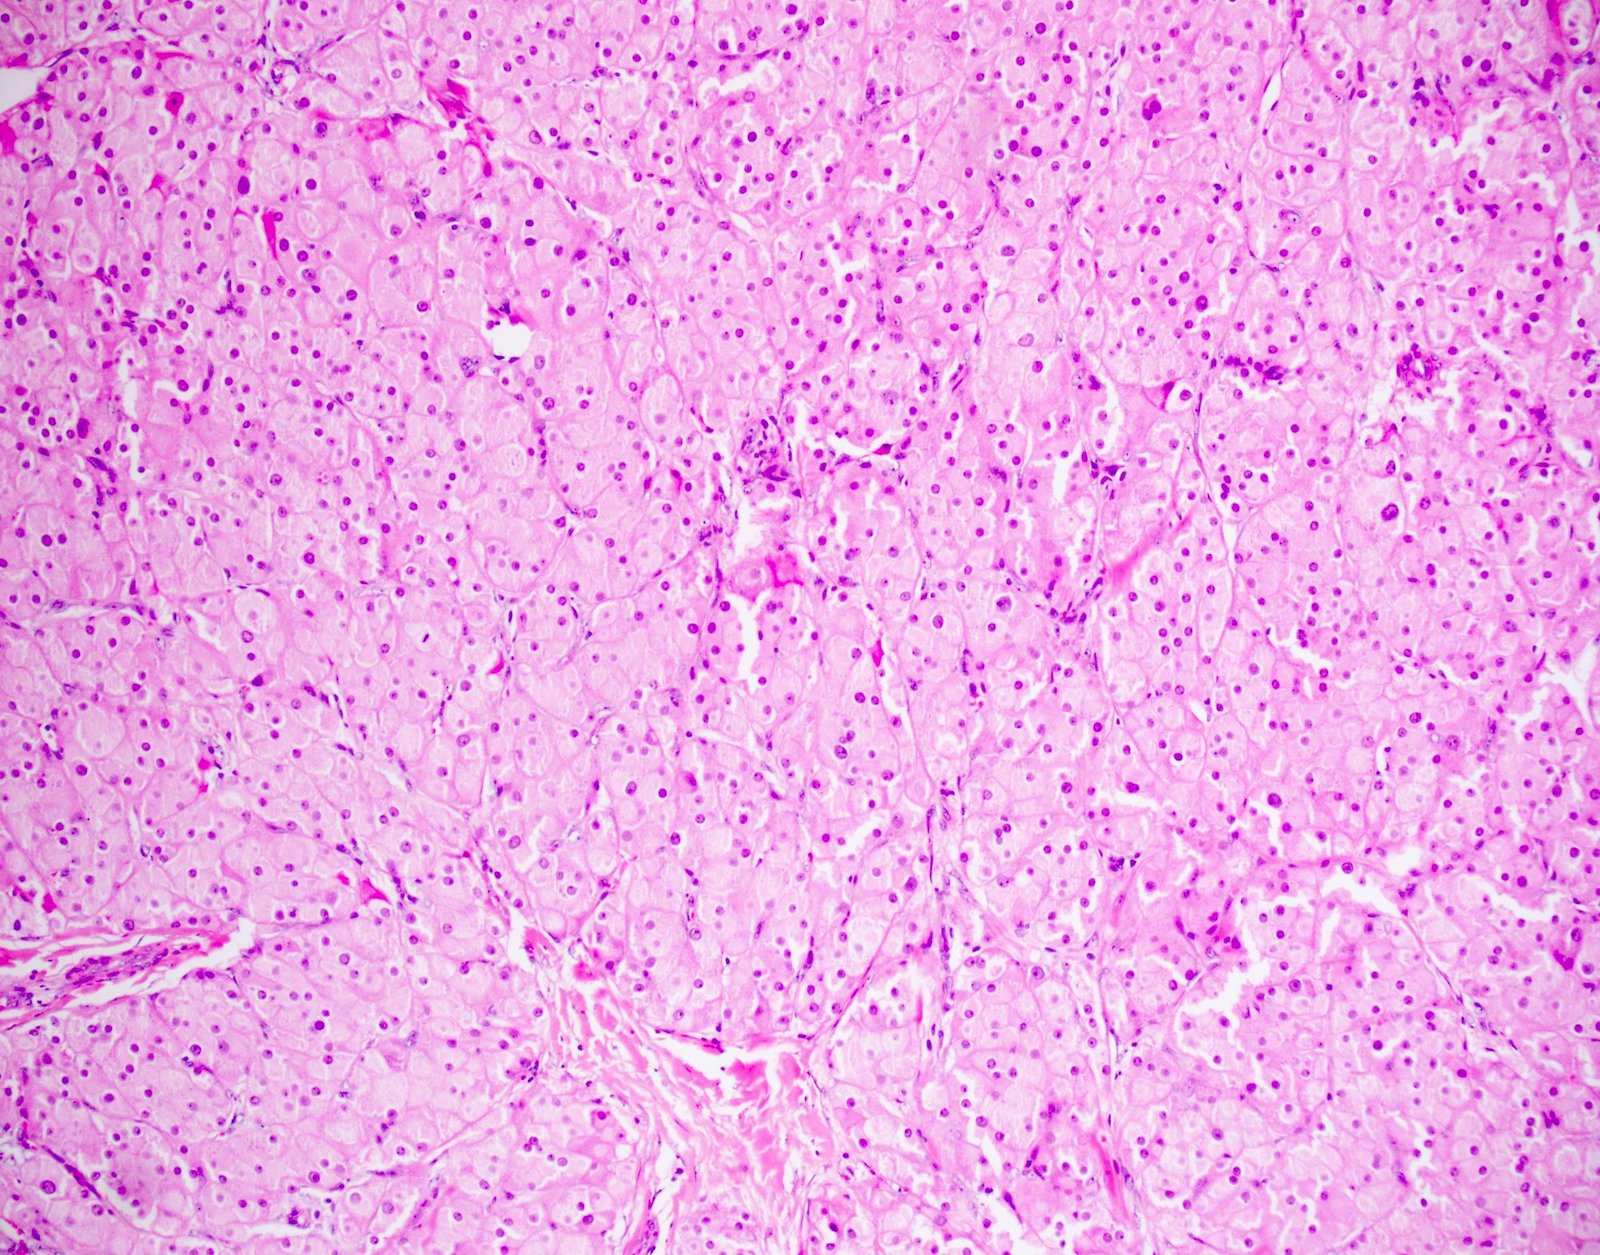

- Architecture:

- Diffuse or nodular with fibrous bands

- Uncommon patterns: insular, trabecular, pseudotubular, ribbon-like, trabecular, spindled and microcystic (Surg Pathol Clin 2018;11:739)

- Cytologic features:

- Polygonal cells with abundant eosinophilic granular cytoplasm, uniform round nuclei and prominent central nucleoli; rarely, nuclei may have a ground glass appearance

- Uncommon cell types: scant cytoplasm, foamy cytoplasm and spindling (Am J Surg Pathol 2002;26:1424)

- Lipofuscin pigment maybe present: golden yellow on H&E stain, red-purple granular appearance on PAS stain

- Binucleated and multinucleated cells may be present

- Reinke crystals: pathognomonic; identified in only up to 30% (degradation / dissolution by formalin fixation); intracytoplasmic, rarely extracellular

- Mitosis: rare

- Mild nuclear atypia permissible

- Occasionally, psammoma bodies, calcification, osseous and adipocytic metaplasia may be identified (Am J Surg Pathol 2002;26:1424)

A 41 year old man was hit in the groin area by a baseball. An ultrasound showed a 3 cm tumor of the testis. On histology, the tumor showed diffuse sheet-like growth of cells with minimal stroma, shown above. The tumor cells were large and polygonal with abundant, slightly granular, eosinophilic cytoplasm. The tumor cell nuclei were round and contained a single prominent nucleolus. Rare intracytoplasmic eosinophilic crystals were identified. The most likely diagnosis of this tumor is which of the following?